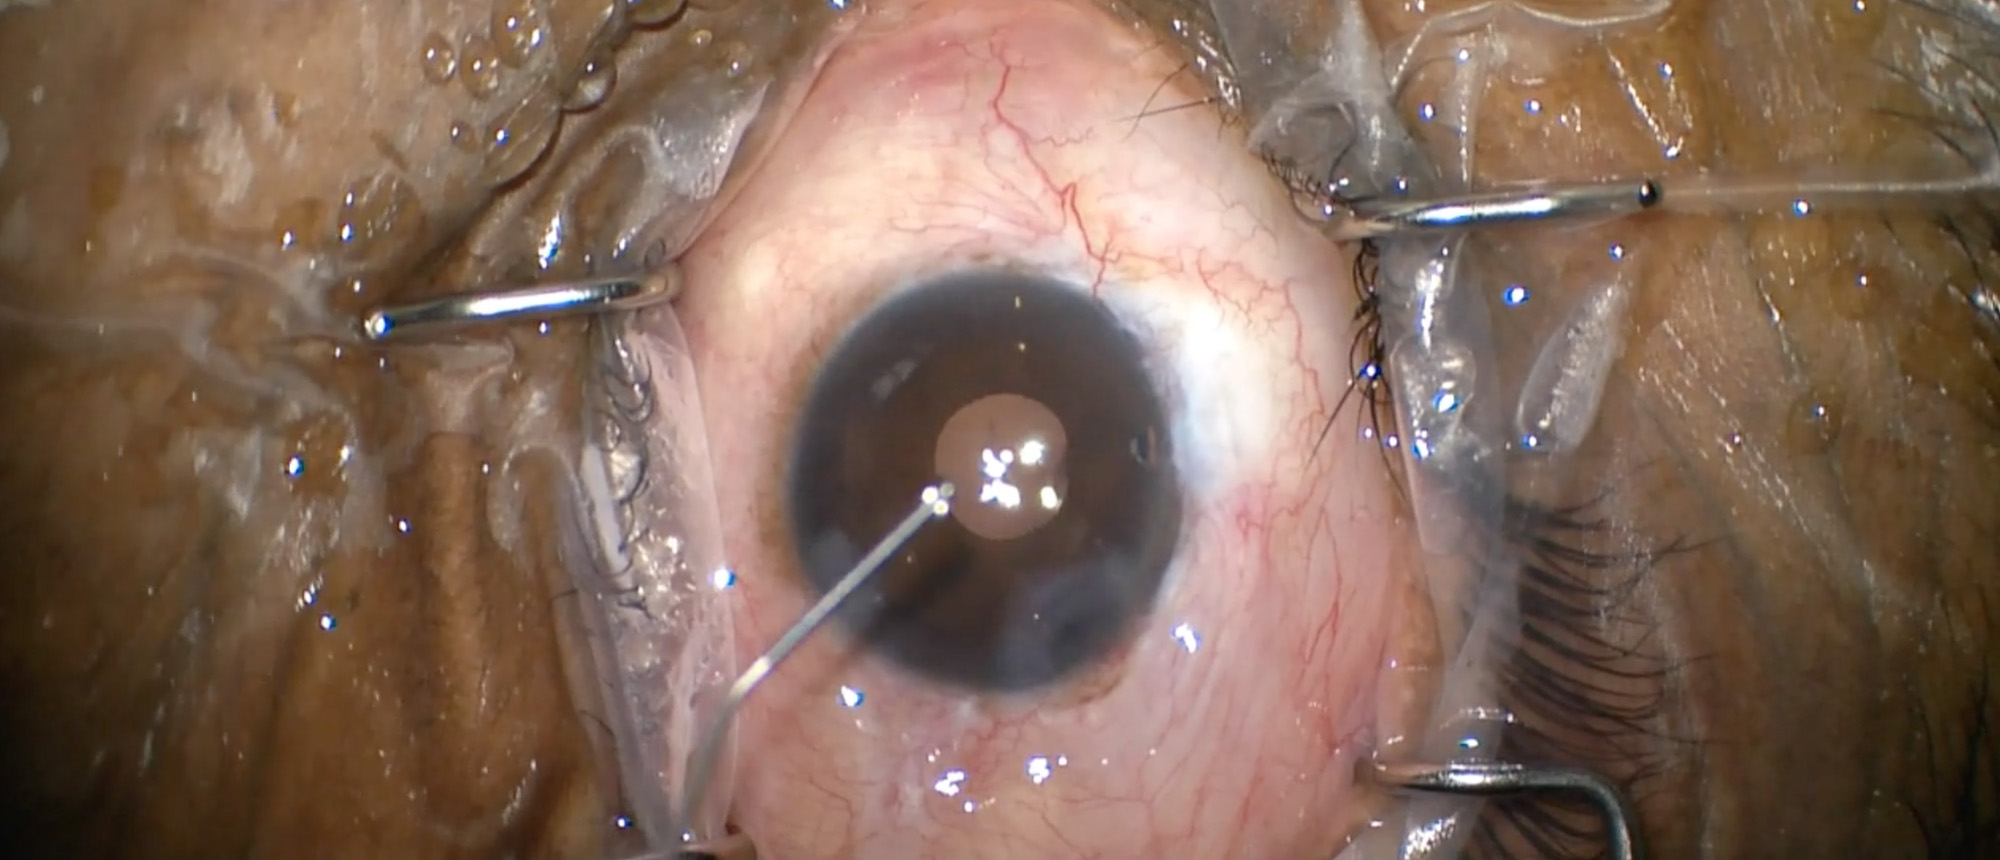

Abstract A healthy patient with prior history of LASIK OU presents with acute-onset decreased vision and eye pain in the left eye. On presentation, patient’s exam was notable for visual acuity of 20/20 in the right eye and 20/60 in the left eye. Intraocular pressure was 11 and 15 in the right and…

Post-LASIK Infectious Keratitis A healthy patient with prior history of LASIK OU presents with acute-onset decreased vision and eye pain in the left eye. On presentation, patient’s exam was notable for visual acuity of 20/20 in the right eye and 20/60 in the left eye. Intraocular pressure was 11 …